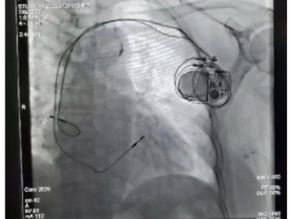

甚麼是心臟起搏器?

在上一期推文中,我們講了心跳慢了怎麼辦。我們將心臟比作“兩室兩廳”的房子。在這一期,我們設想,如果房子總開關經常“跳閘”失靈(心動過緩),那能不能在人體中附加一個電源維持供電(心跳)? 在這樣的想法下,人工心臟起搏器誕生了。心臟起搏器是一種由電池供能、植入體內的電子儀器。它...